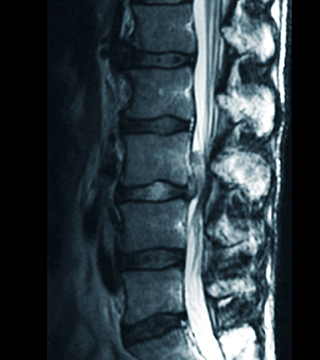

흔히 50대에 가장 많이 발생하는 꼬부랑 노인병으로 알려져 있으며 허리디스크와 증상이 비슷합니다. 오랜 시간 뼈, 인대, 디스크 등이 퇴화되면서 척추관이 좁아져 발생하는 질환입니다.

척추내 신경이 눌리면서 여러가지 증상을 일으키는 질환으로, 다리가 저리고 당기는 통증, 힘이 빠지거나 감각 이상의 증상이 나타납니다.